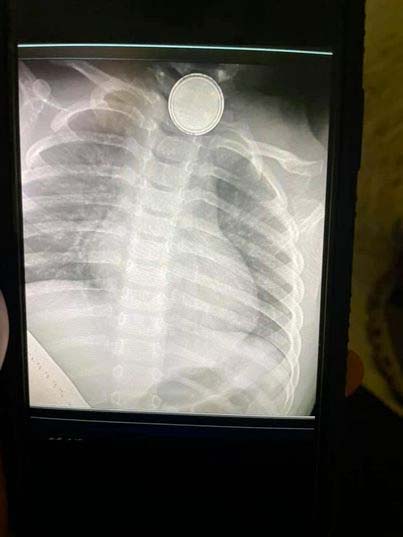

Hon körde sin dotter direkt till en lokal akutmottagning där röntgen bekräftade vad Trista fruktade – dottern hade verkligen svalt det lilla batteriet!

Det hade också orsakat ett hål i matstrupen.